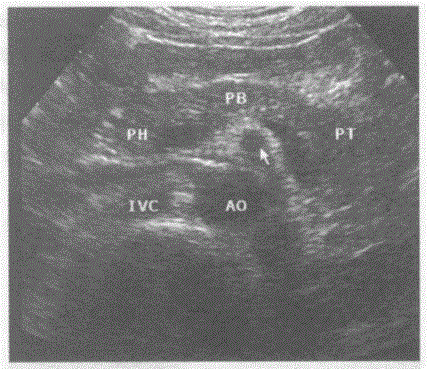

问题 下图是剑突下横切正常超声图像,请回答箭头所指部位声像图的断面解剖名称.

选项 A.腹腔动脉 B.肠系膜上静脉 C.肠系膜下动脉 D.肠系膜上动脉

答案 D